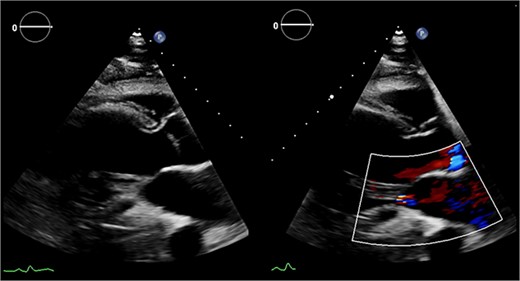

Echocardiography (Fig. 1) and cardiac magnetic resonance imaging revealed a dilated LV [left ventricular ejection fraction (LVEF) of 25%] and a large aneurysm (9.3 × 9.5 cm) involving the basal mid-inferoseptum and basal inferolateral wall with evidence of thrombus. These regions were non-viable, with transmural infarction. The mitral valve (MV) leaflets were thin but the tips, especially of the posterior mitral valve leaflet, were tethered and tented towards the LV apex resulting in severe functional MR. The left atrium (LA) was significantly dilated. The patient was admitted for medical management including aggressive diuresis. Following multidisciplinary team (MDT) discussion, surgical intervention was planned (aneurysmectomy with either MV replacement or repair). Mechanical circulatory support and cardiac transplantation were considered and deemed appropriate for rescue therapy.

Preoperative echocardiography: large LV aneurysm below the posterior mitral valve leaflet tethering it open in systole resulting in severe functional mitral regurgitation.